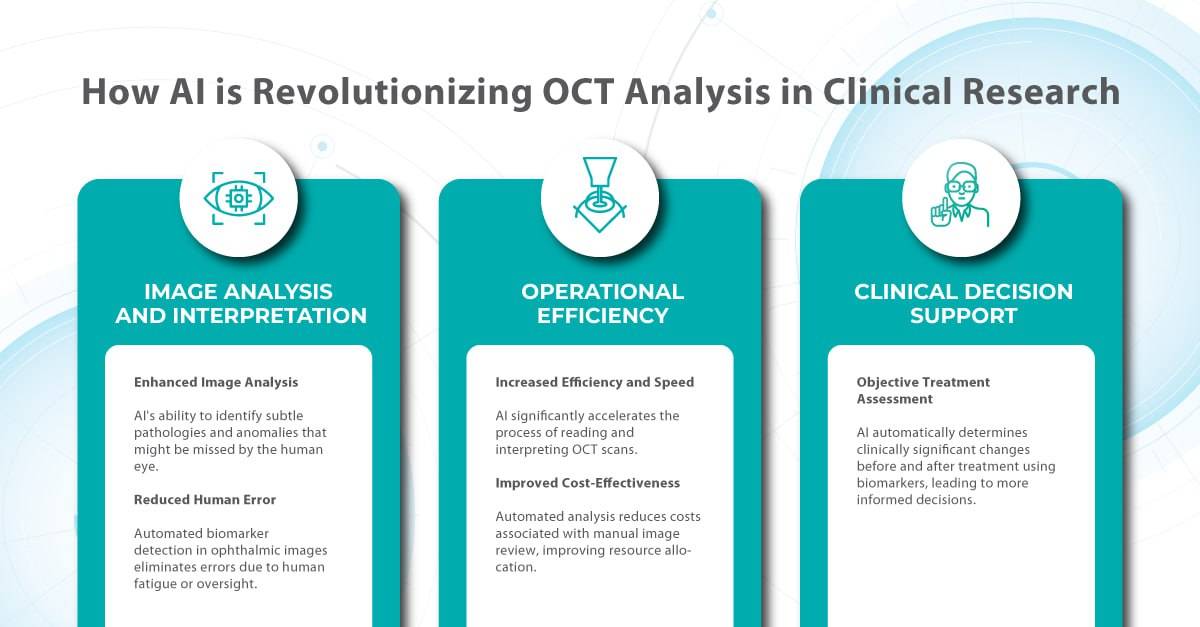

Here is where AI enters the game. With its ability to rapidly analyze vast amounts of data and detect subtle patterns, AI is revolutionizing how we approach clinical trials for ophthalmic drugs.

In ophthalmology, AI-powered analysis of OCT scans can provide precise, quantitative measurements of retinal thickness, fluid volume, and other biomarkers relevant to diseases like diabetic retinopathy and age-related macular degeneration. These measurements can aid in diagnosis, disease staging, treatment monitoring, and prediction of treatment response.

By automating the analysis of OCT scans, AI not only streamlines the process but also uncovers subtle details and patterns that might be missed by human observation.

Enhanced by AI precision enables more accurate identification and quantification of biomarkers, leading to better patient stratification, treatment monitoring, and prediction of therapeutic responses.

While semi-quantitative scoring systems offer some level of objectivity, the field is rapidly evolving towards more quantitative and automated approaches. This shift is driven by advancements in standardization, sophisticated image analysis techniques, and the rise of machine and deep learning.

In some clinical scenarios, automated image quantification can surpass manual assessment in objectivity and accuracy, interpreting subsequent changes with greater precision and clinical relevance by establishing thresholds for disease states. Unlike physical biomaterials, medical images are easily and rapidly shared for analysis, facilitating automated, reproducible, and blinded biomarker extraction.

AI can automate this process, rapidly analyzing medical imaging and extracting relevant information to determine patient eligibility. This reduces the burden on staff and allows for faster identification and enrollment of suitable participants, streamlining patient selection and ultimately leading to more efficient and successful clinical trials.

AI-powered image analysis offers a crucial advantage: reducing variability in interpretation.

AI algorithms can standardize the imaging overview process by consistently identifying and quantifying key biomarkers, ensuring that different readers arrive at similar conclusions.